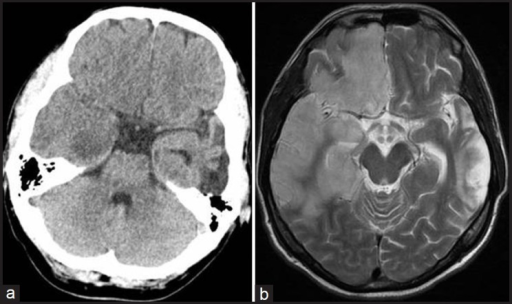

What's the Diagnosis?